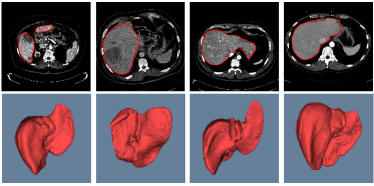

Refer to caption

Figure 7: 2D images of segmentation results of four challenging cases in axial, sagittal, and coronal planes with the ground truth in blue. The initial liver region generated by CNNs is in yellow and the final refined result is in red

Figure 8: 3D visual representation of livers segmented by our method on the same four cases as shown in Fig. 7. The first row shows the ground truth; the second and third rows present the surface distance error (mm) of 3D CNNs and the proposed segmentations with the ground truth

Figure 7 illustrates our segmentation and manual delineations for four challenging cases in coronal, sagittal, and axial planes. The initial liver region generated by 3D CNNs is in yellow, the final refined result is in red and the manual delineation is in blue. The first column shows a case with highly inhomogeneous appearances. The last three columns display three representative livers containing tumors. Particularly, some tumors locate on the boundary, which makes it more difficult to automatically delineate the accurate boundary. As can be seen, 3D CNNs can detect the most liver region and the refinement model can obtain a higher agreement with the ground truth. Figure 8 depicts the corresponding 3D visualization results of 3D CNNs and the proposed method for the cases shown in Fig. 7. The 3D visualization of errors is based on the MSD error between the segmentation result and the ground truth. As can been seen, the MSD errors of the 3D CNNs for the four cases (from left to right) are 22.1 mm, 12.6 mm, 62.6 mm and 74.5 mm, respectively, while the MSD errors of the proposed model are 17.0 mm, 11.2 mm, 22.1 mm and 15.3 mm, respectively. Obviously, the proposed approach can obtain lower errors in terms of MSD.